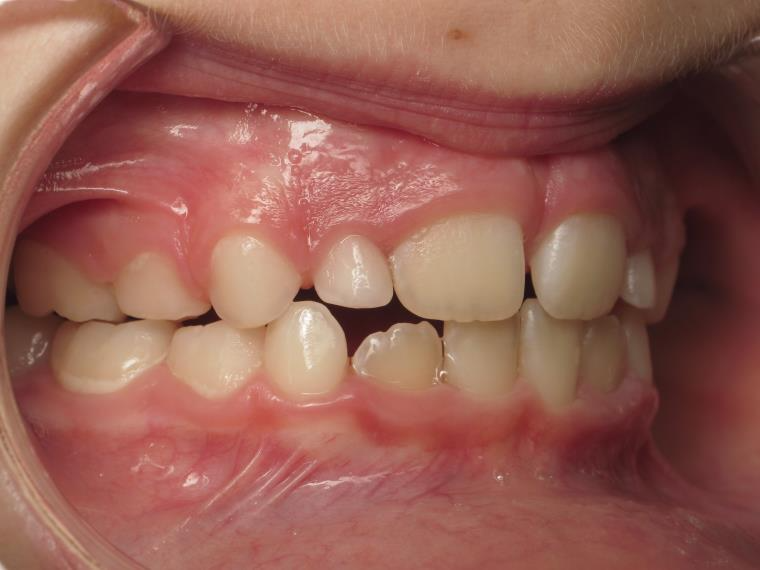

sectionnel multibagues

bilan début fin de traitement